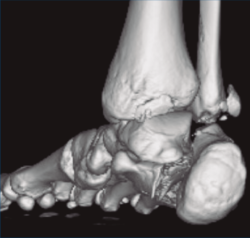

Figura 3. Desplazamiento entre fragmento anteromedial (sustentaculum tali) y posterolateral (tuberosidad).

Se trata de un varón de 19 años que ingresa en reanimación tras precipitarse desde una altura de aproximadamente 10 metros. El paciente presenta una fractura estallido de L3 con afectación del canal medular junto con una fractura del vértice inferior de L4, así como una fractura luxación de calcáneo, asociada a una fractura del maléolo peroneo y del maléolo tibial posterior (Figuras 1 a 6) diagnosticadas mediante TC total body (por eso no se dispone de radiografías simples al momento del ingreso). Como podemos comprobar, se trata de una fractura de doble trazo de tipo hundimiento/depresión de la carilla articular (Figuras 5 y 6).

Figura 4. Luxación fragmento posterolateral.

Figura 6. Fractura de doble trazo; se evidencia afectación de la articulación calcaneocuboidea.